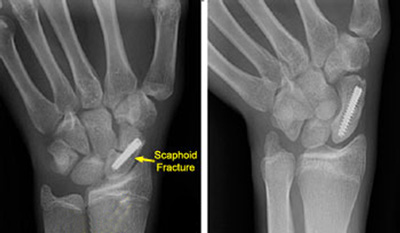

(Left) This x-ray shows a scaphoid fracture fixed in place with a screw. (Right) This x-ray was taken 4 months after surgery. The fracture of the scaphoid is healed.